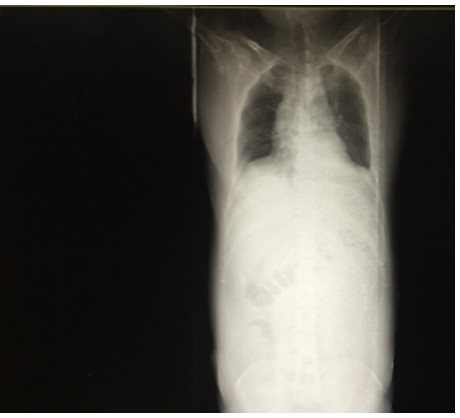

SAP发生呼吸衰竭的原因很复杂,其原因有以下几种。(1)SAP因为炎症反应导致的ARDS(图 1),这是普遍认为的一种原因,但实际上ARDS在SAP患者呼吸衰竭中很多时候是非主要原因。SAP急性期虽然病情进展很快,出现多脏器功能损伤,甚至休克,有类似于脓毒症和感染性休克样的表现,但其炎症反应并不如脓毒症这么强烈,大量的研究可见SAP发生过程其IL-6很少过千,而脓毒症则IL-6动辄大于5 000或10 000,SAP两肺影像学也很少有典型的非心源性肺水肿的双侧阴影,超声下也很少有“B线”表现。但胆道感染引起的脓毒症合并SAP的患者,其ARDS发生率会明显上升。现在随着高脂血症胰腺炎的增加,部分患者到院时同时存在糖代谢障碍,合并有糖尿病酮症,入院前后出现糖尿病酮症昏迷,有些患者会伴有呕吐误吸或者插管时误吸,这类患者在急性期会出现误吸相关的ARDS。(2)SAP是腹腔重症的一种,急性期因为腹膜后急性胰周液体积聚和急性胰周坏死物积聚,导致腹腔压力进行性升高,随之出现横膈抬高,两肺压缩,从而导致“小肺”,这和ARDS的“baby lung(小肺)”不同(图 1: ARDS;图 2、3: 腹内压14 mmHg和23 mmHg的对比,明显看到图 3呈现横膈抬高引起的小肺)。因横膈位置上抬导致小肺是SAP呼吸衰竭的主要原因。(3)两下肺不张(图 4)和胸腔积液(图 5):这两个原因也是导致SAP呼吸衰竭的主要原因,因为膈下刺激,导致两下肺的不张和大量胸腔积液常见于SAP患者,这两种原因导致的呼吸衰竭也和ARDS不同。(4)其他原因:胸腔出血、肺梗死和气胸亦可见于SAP相关呼吸衰竭,但相对少见。

| 图 1 ARDS |